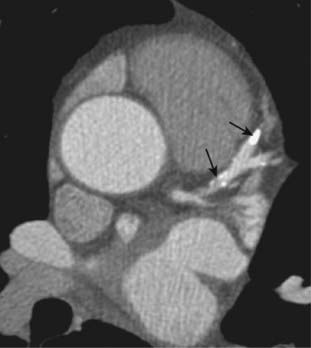

imageOn both MRI and CT, the diagnosis rests on identification of the intimal flap that separates the true (original) from the false lumen (canal created by the dissection) (Fig. 9-28).

image

Figure 9-28 Aortic dissections, types A and B.

A, An intimal flap is seen to traverse both the ascending (solid black arrow) and descending aorta (dotted black arrow). This is a Stanford type A dissection. B, There is a normal-appearing ascending aorta (dotted white arrow) while an intimal flap is noted by the black line traversing the descending aorta (solid black arrow). The intimal flap is the characteristic lesion of an aortic dissection. The smaller lumen is usually the true (original) lumen, and the larger, false lumen is actually a channel that has been produced by blood dissecting through the media.